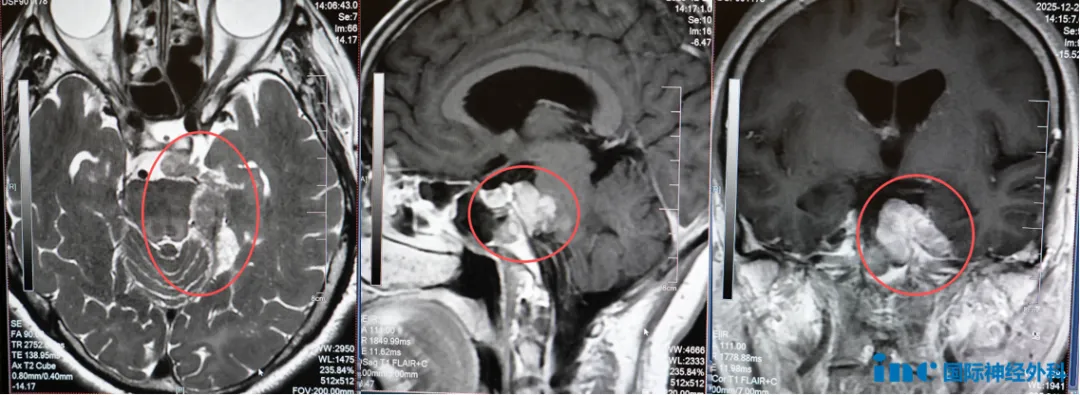

在苏州大学附属儿童医院,两位特殊患儿等待诊治。11岁男性患儿小正,确诊右侧桥小脑角区间变性室管膜瘤(WHO 3级)已五年,历经多次手术及放化疗。2025年末复查显示肿瘤从16×14mm进展至39×27mm,伴有右耳听力丧失及面神经症状加重。